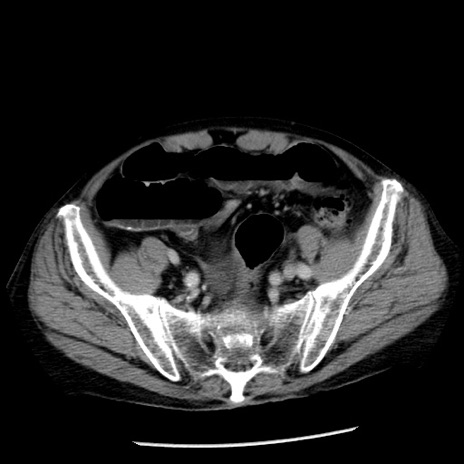

症例26(横断像)

【症例】80歳代男性

【主訴】嘔吐

【現病歴】昨晩2回嘔吐あり、今朝になっても嘔吐あり。来院。

【既往歴】胃潰瘍

【身体所見】意識清明、BT 37.6℃、BP 166/95mmHg、HR 100bpm、SpO2 97%、腹部:平坦・軟、腸蠕動音聴取良好、圧痛なし。

【データ】WBC 21900、CRP 1.46